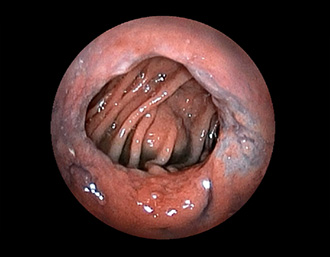

症例1:胃潰瘍(37才、男性)

①胃潰瘍(Stage A1)

健診:胃レントゲン検査で、胃角部ニッシェを指摘され当院受診。

胃角部小弯に、深くて大きな、大きさ約10mmの胃潰瘍(stage 1)があり、潰瘍底は一部白苔はみ出しを認める。エソメプラゾールマグネシウム水和物投薬で治療開始しました。

通常画像